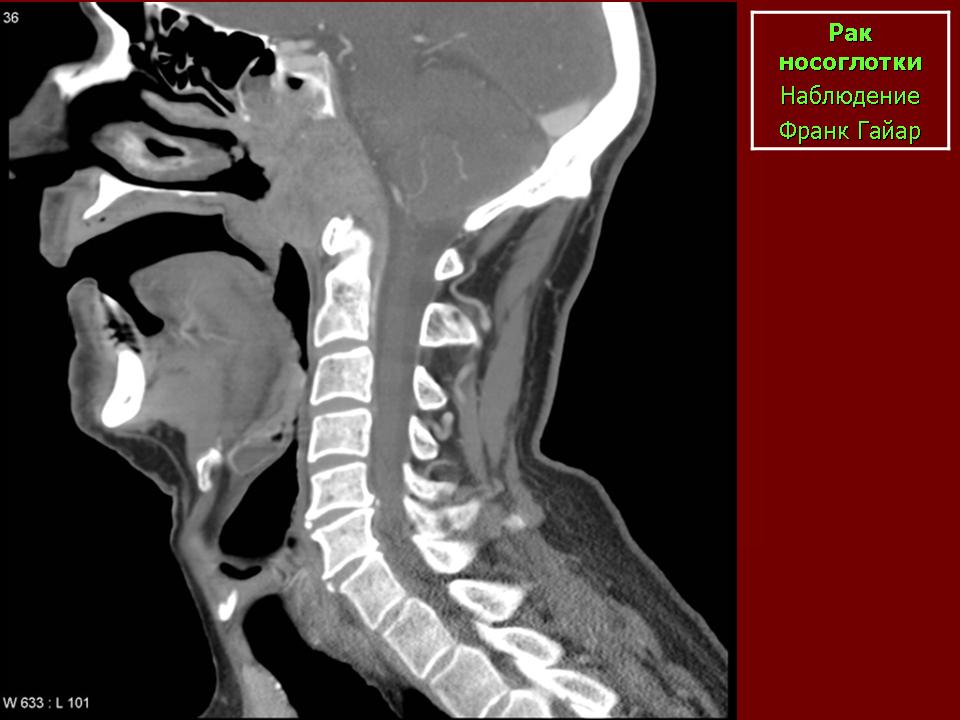

ЛОР. Онк. Рак носоглотки. +

Рак носоглотки